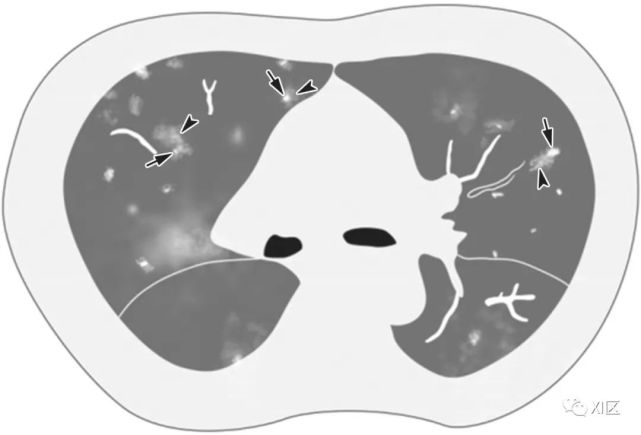

图25 47岁女性COVID-19肺炎患者持续发热(38.8°C)3天的典型CT表现演变。(a) 在第3天时,在右下叶显示一个小的胸膜下GGO合并部分实变区;(b)第7天,GGO扩大区合并部分实变的小叶间和小叶内间隔增厚(疯狂铺路模式);(c)第11天,初始GGO的部分实变,新的胸膜下实变区;(d)第20天,观察到残留GGO和实质条带的持续吸收。所有图像都具有相同的窗位-600HU和窗宽1600HU。

Feng Pan, Tianhe Ye, Peng Sun, et al. Time Course of Lung Changes On Chest CT During Recovery From 2019 Novel Coronavirus (COVID-19) Pneumonia. Radiology. Published Online:Feb, 13, 2020. https://doi.org/10.1148/radiol.2020200370